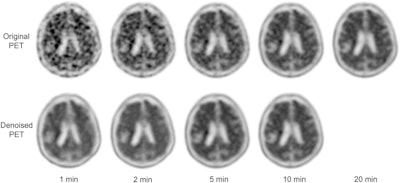

PET images acquired from both the standard scanning time of 20 minutes and reduced scanning times of one, two, five, and 10 minutes were reconstructed by the MCDNet-2 denoising model for each patient and then compared. The quality of the PET images was quantitatively evaluated using objective metrics, while two radiologists performed subjective evaluations using a qualitative 5-point grading system.

The denoised results of the one-minute and two-minute PET images were overly smooth and blurry, the researchers reported. The denoised results of the five-minute and 10-minute PET images, however, showed a high similarity with the ground truth 20-minute PET images.